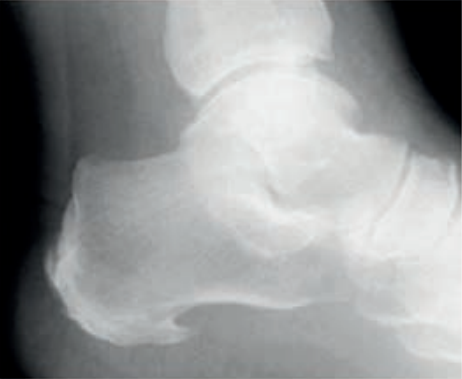

Którą strukturę anatomiczną i w jakiej projekcji uwidoczniono na radiogramie?

A. Staw kolanowy w projekcji tunelowej.

B. Wyrostek dziobiasty w projekcji skośnej.

C. Guz piętowy w projekcji osiowej.

D. Wyrostek łokciowy w projekcji osiowej.